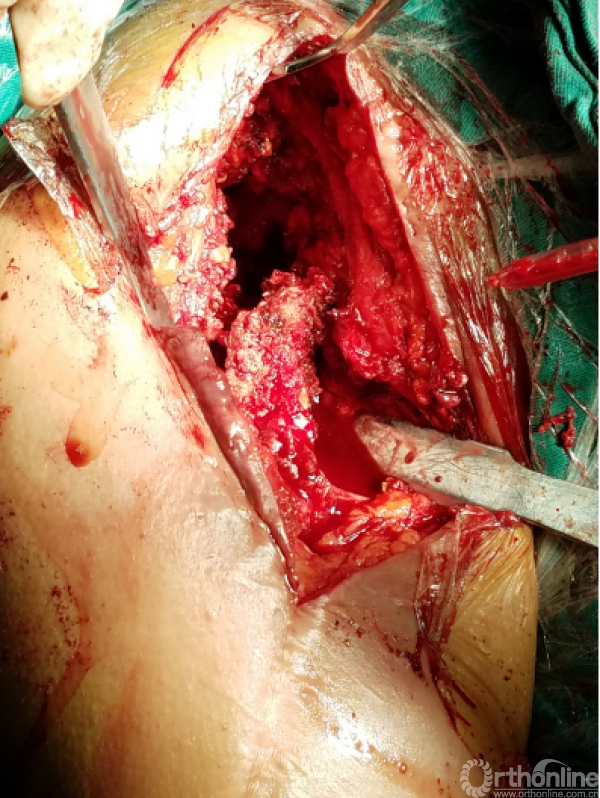

困难重重:

1、广泛粘连,解剖层次不清

2、广泛点状出血灶

3、分不清间隙

4、盂肱关节正常结构位置改变,关节囊瘢痕挛缩替代

5、屈曲外旋看不见关节间隙活动

咬出增生骨痂及清理瘢痕组织后显露出原肩袖缝线,杂乱,完整,表面见有脓性组织

瘢痕发硬,变性,周围包裹纤维软骨痂

由于解剖结构紊乱,头静脉已消失。旋肱后动脉,弓状动脉剥离时出血,位于外侧转弯处,行填塞止血。

显露出肱骨头假体柄处

开始向内上扩大显露

注意事项:  肱骨头内移至喙突处,位于后内侧下方已有骨桥连接

特别小心腋鞘及臂丛神经

提示无法顺利脱位!!!

小心咬出间隙后,牵引肘关节前屈肩关节后伸外旋,拉钩撬拨脱位!!

关节盂正常结构消失,至喙突偏内侧部位,上方紧贴肩峰下,仍然有骨质可用!